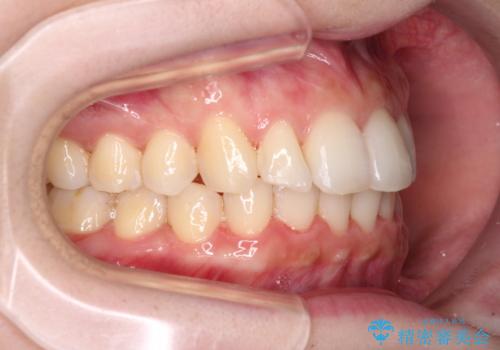

半年もせずにインビザラインを全く使用することができなくなってしまったので、治療開始から1年ほどでワイヤー矯正へ変更することとなりました。

ワイヤー矯正へ変更してからはあっという間に治療が進み、1年弱で終えることができました。